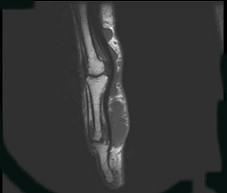

问题 女,77岁,发现右手部肿块二周,请结合影像图像提出最可能的诊断 ( )

选项 A、血管瘤 B、以上都不是 C、多发性腱鞘囊肿 D、骨囊肿 E、肌内脓肿

答案 C